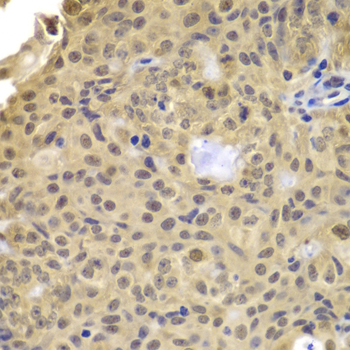

Immunohistochemistry of paraffin-embedded human well-differentiated squamous skin carcinoma using CCNA2 antibody at dilution of 1:100 (x400 lens).

Immunohistochemistry of paraffin-embedded mouse kidney using CCNA2 antibody at dilution of 1:100 (x400 lens).